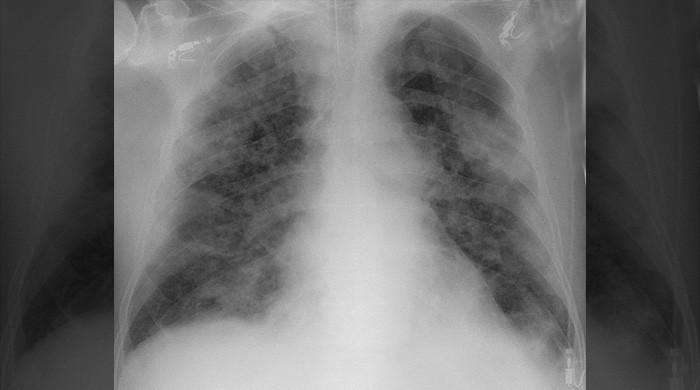

‘COV-RAID’ has an accuracy of more than 90%, uses chest x-rays to detect whether a patient is suffering from coronavirus